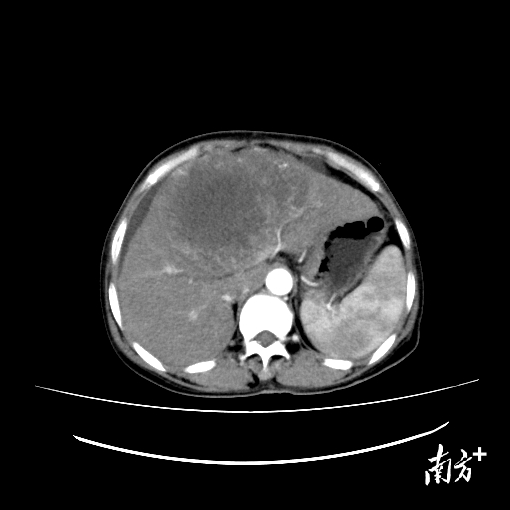

治疗前CT检查发现肿瘤直径最大13厘米。

入院后检查结果显示,她的肝脏有一颗直径达13厘米的肿瘤,属于巨块型肝癌。由于靠近第一和第二肝门,不适宜手术治疗。